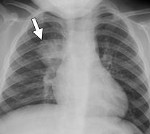

Рентгенологическая картина при очаговой пневмонии может быть вариабельна. В типичных случаях с помощью рентгенографии легких определяются очаговые изменения на фоне периваскулярной и перибронхиальной инфильтрации. В сомнительных случаях рентгенологические данные должны уточняться с помощью КТ и МРТ легких, бронхоскопии.

Если врач предполагает пневмонию, то диагноз следует подтвердить флюорографией, которая покажет степень инфекционного поражения легких. Для идентификации патогенного микроорганизма собирают и исследуют образцы мокроты. В целях уточнения диагноза также делают анализы крови.

Основной метод диагностики пневмонии – рентгенологическое исследование (на снимках области поражения выглядят как темные пятна разного размера и формы). Для определения возбудителя болезни и его чувствительности к терапии проводятся клинические анализы крови, мокроты.